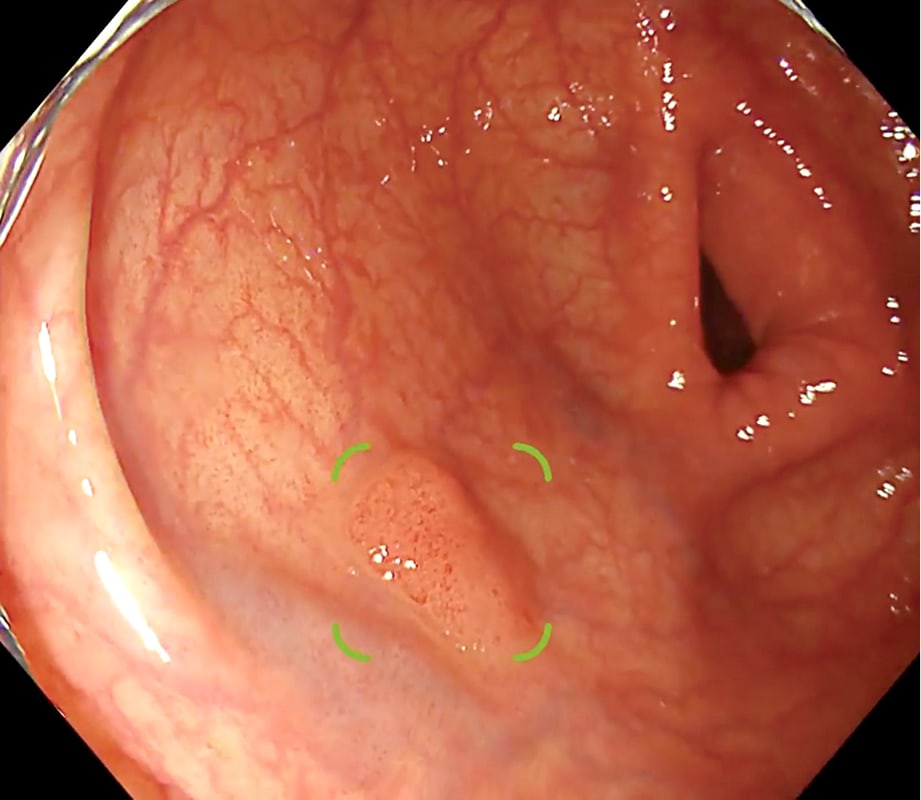

Chest nodule detection support technology that makes an effective diagnosis possible

EIRL Chest Nodule supports the interpretation process by identifying findings suggestive of lung nodules from chest X-rays that are larger than 5 mm and smaller than 30 mm. The sensitivity of the specialized-radiologist and the non-specialized radiologist interpreting the images with the software increased by 9.9% and 13.1 % respectively, suggesting an improvement in diagnostic accuracy.